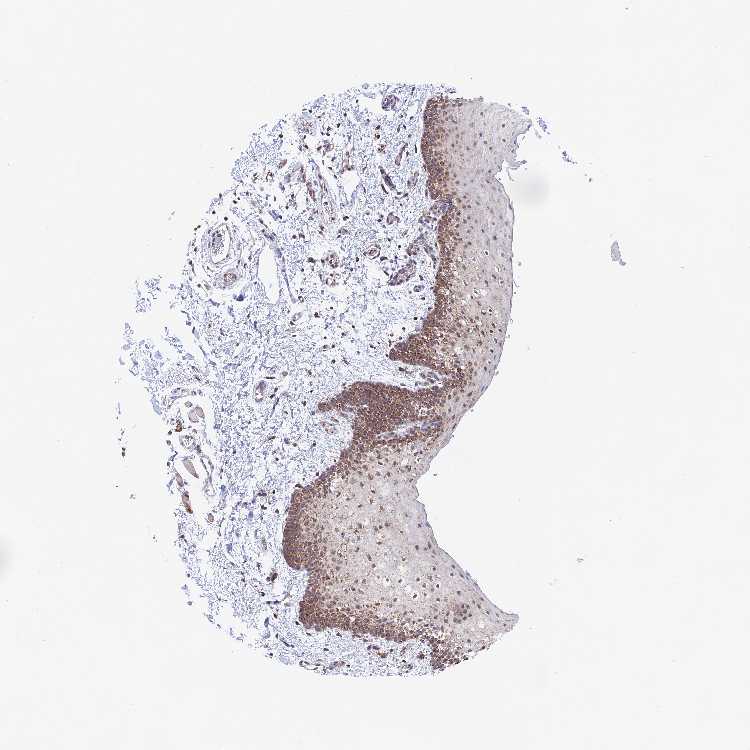

TISSUE PRIMARY DATA ORAL MUCOSA Show tissue menu

ORAL MUCOSA - Antibody stainingi

Antibody staining in the annotated cell types in the current human tissue is reported as not detected, low, medium, or high, based on conventional immunohistochemistry profiling in selected tissues. This score is based on the combination of the staining intensity and fraction of stained cells.

Each image is clickable and will lead to virtual microscopy that enables deeper exploration of all samples and also displays staining intensity scores, fraction scores and subcellular localization as well as patient and tissue information for each sample.

Antibody HPA042826

Squamous epithelial cells Medium